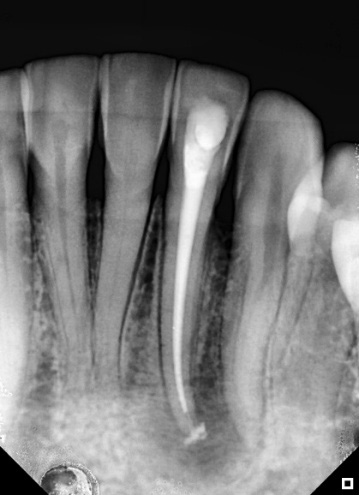

The first session involved anesthesia, endodontic access correction, absolute isolation, and root canal preparation. During the mechanical chemical preparation, constant irrigation and patency of the canal were used at each file change. The first session concluded with the canal being filled with the intracanal dressing BIO-C® TEMP® (Angelus), followed by a radiograph to confirm that the canal had been filled (Figure 2).

Figure 2: BIO-C® Temp medication applied to the canal after the preparation had been completely carried out